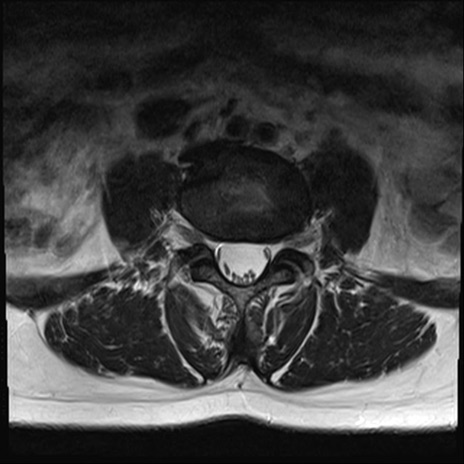

【整形】TIPS症例4 腰椎MRI T2WI(横断像)

腰椎MRI

横断像と矢状断像